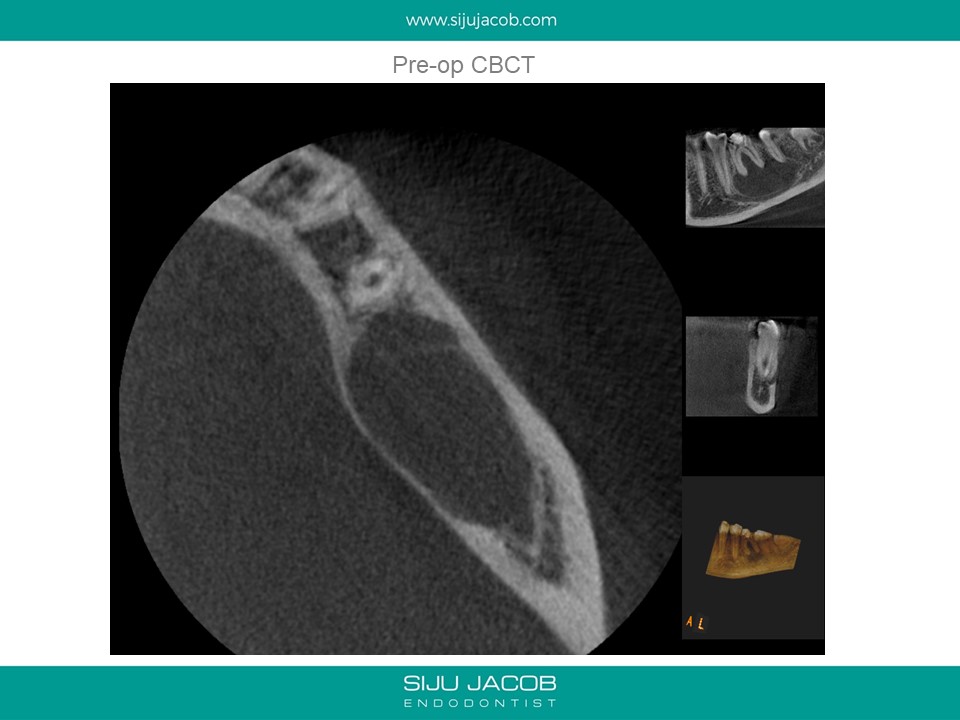

This was a 15 year old girl with a large peri-apical lesion in relation to the the left mandibular first molar. The tooth had a guarded restorative prognosis. The goal of endo in this case was to hold the tooth for a longer period before placing implants and also get some bone to fill in which would make implant placement more viable. I held the tooth with calcium hydroxide dressing for 5 months, saw some bone-fill and obturated the tooth. A crown was also placed. 3-year recall shows the tooth still going strong.